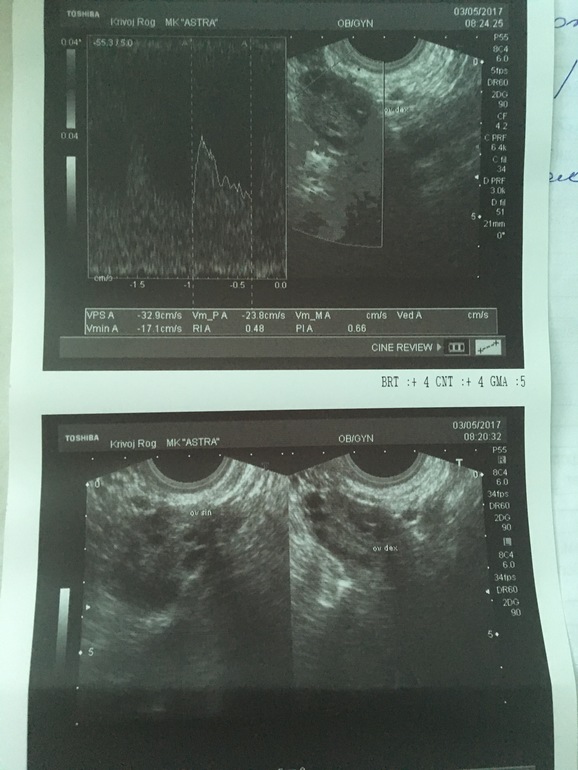

Конечно я не узист, но в виду моих хождений по узи, я вижу жт на первом фото и на нижнем справа. По крайней мере мне на такие пятна говорили что это жт. Фолики более круглые и окрашены в сплошной темный.

На первом фото действительно похоже на жт, а слева как раз его кровоток. А жидкость видели?